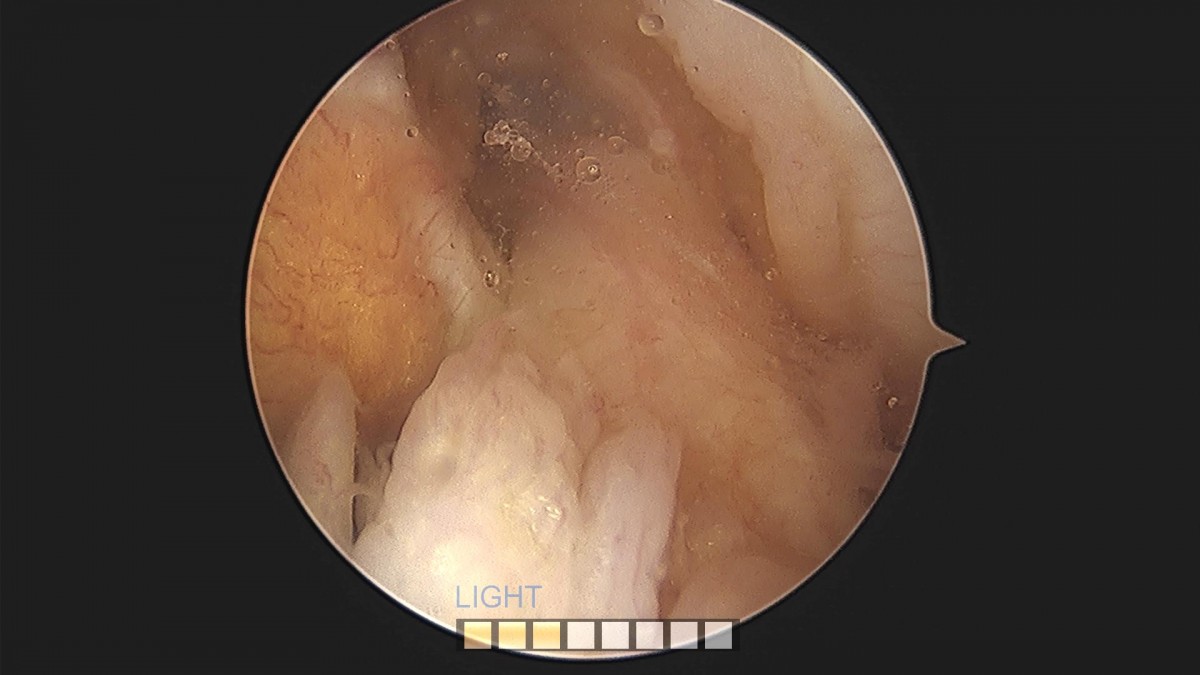

배우한원장님 대퇴골다발성천공술 (4684)양경O 환자

작성자 최고관리자 댓글 0건 조회 1,209회 작성일 22-05-09 12:45